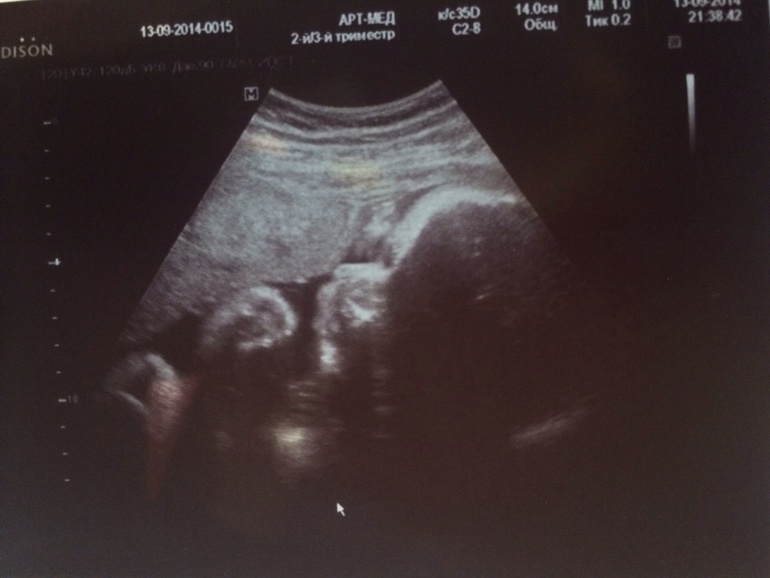

Вчера были на УЗИ!!!

Наш любимый мальчик так вырос!!)))

Лежал зевал, открывал ротик и как всегда закрывался ручками!!

Губы большие такие, как у мужа, волосики отросли длинные!!!)))

Весим 1884 г., все у нас хорошо, плацента только ей не очень понравилась!

Одно обвитие, говорят все свободно вокруг шеи и малышу это не мешает!

Лежим головой вниз, как я и думала, что сынуля бил меня ножкой вверх!!))